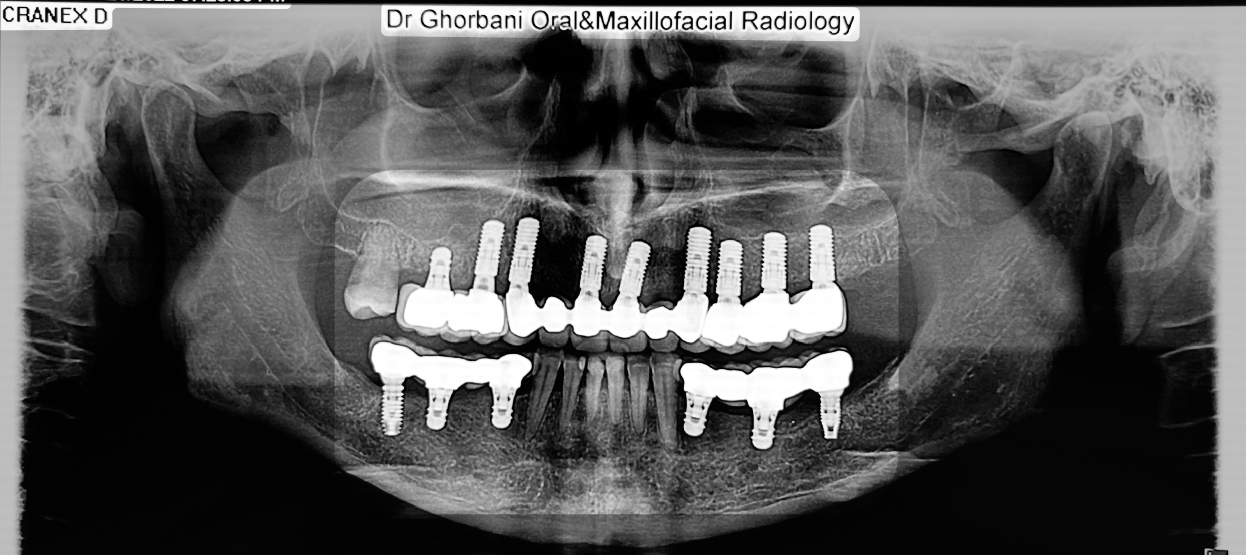

کشیدن دندانهای پوسیده و همزمان ایمپلنت

در آوردن روکشها,کشیدن دندانهای پوسیده و کاشت ایمپلنت اشترومن و پیوند استخوان در یک جلسه.